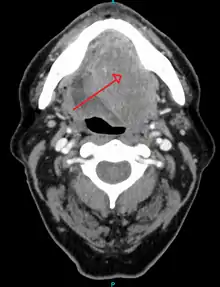

- better assess the size of the lesion (CT scan, MRI or PET scan with 18F-fluorodeoxyglucose (FDG)),[34]: 143

- spread to the lymph nodes (CT scan) or